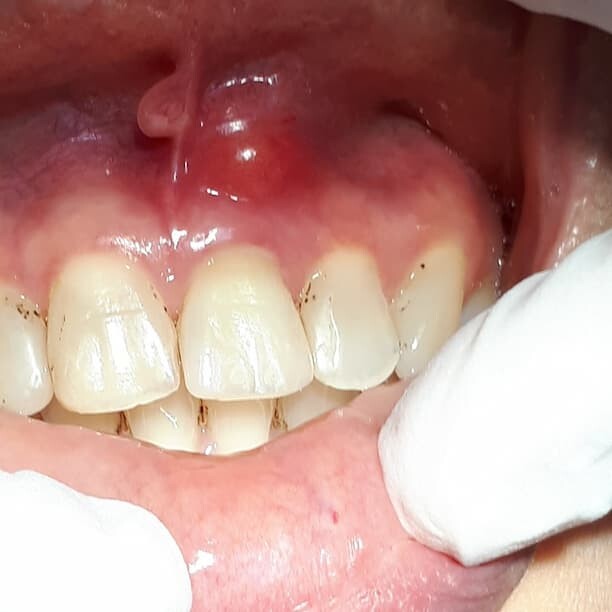

Abscessed Tooth: What You Need to Know

An abscessed tooth is a pocket of pus that can form in different parts of a tooth as a result of a bacterial infection. It’s sometimes called a dental abscess. An abscessed tooth causes moderate to severe pain that can sometimes radiate to your ear or neck.

Left untreated, an abscessed tooth can turn into a serious, life-threatening condition. Read on to learn more about the different types and how to recognize them.

swollen, red gums